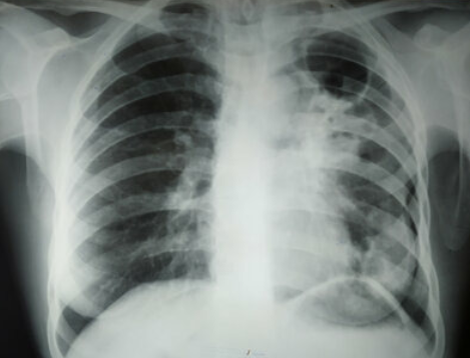

АСКОРБИНОВАЯ КИСЛОТА УБИВАЕТ ТУБЕРКУЛЕЗ..

Израильские ученые выяснили, что Аскорбиновая кислота способна убивать микобактерии туберкулеза... Давайте разбираться с самого начала. Туберкулез, как известно, вызывается легко адаптирующейся бактерией M. tuberculosis. В 2011 году, по статистике ВОЗ, от туберкулеза во всем мире умерли 1,4 миллиона человек, а около 8,7 миллиона заболели. Резистентные микобактерии, которые не поддаются лечению стандартными антибиотиками, представляют большую угрозу даже в 21 веке: около 650 000 во всем мире больны мультирезистентным туберкулезом (MDR-TB), 9% из которых имеют особо устойчивую форму (XDR-TB) Открытие израильских ученых повысило интерес к проблеме микобактерий туберкулеза, резистентных к изониазиду – мощному препарату первого ряда. Главным автором исследования стал доктор Уильям Джейкобс, профессор микробиологии, иммунологии и генетики в Колледже медицины имени А. Эйнштейна. Доктор Джейкобс является также членом Национальной академии наук и сотрудником Медицинского института Говарда Хьюз